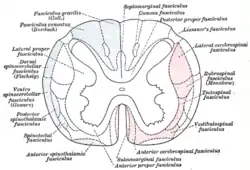

Diagram of the main tracts within the spinal cord - spinothalamic fasciculus is labelled at bottom left | |

The spinothalamic tract consists of two adjacent pathways: anterior and lateral. The anterior spinothalamic tract carries information about crude touch. The lateral spinothalamic tract conveys pain and temperature.

In the spinal cord, the spinothalamic tract has somatotopic organization. This is the segmental organization of its cervical, thoracic, lumbar, and sacral components, which is arranged from most medial to most lateral respectively.

There are two main parts of the spinothalamic tract:

- The lateral spinothalamic tract transmits pain and temperature.

- The anterior spinothalamic tract (or ventral spinothalamic tract) transmits crude touch and firm pressure.